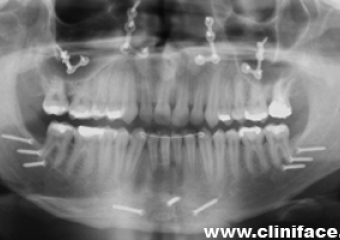

Rx inicial